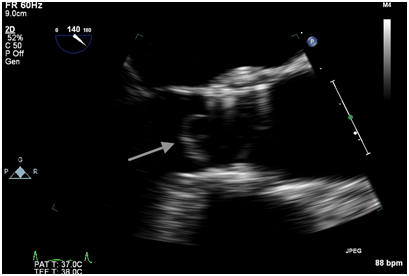

Figure 1A Intraoperative TEE post valve deployment showing the echodensity prolapsing across the valve prosthesis into the aorta.

Immediately after the prosthetic valve deployment, intraprocedural TEE revealed a 20 x 9.5 mm mobile echo density attached to the ventricular side of the strut along the right coronary cusp. The structure intermittently prolapsed through the leaflets of the newly placed valve prosthesis during systole (Figure 1A, 1B). However, only mild (1+) central aortic regurgitation was noted (Figure 2). There was no left ventricular outflow tract obstruction and the prosthetic valve leaflet excursion was otherwise normal. The peak and mean aortic valve gradients were 7 and 4 mm Hg respectively post deployment.